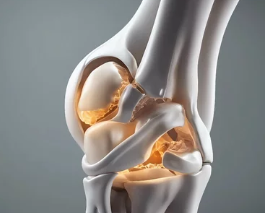

5. 퇴행성 관절염 진단 방법

검사 설명

| X-ray(방사선 촬영) | 관절 간격 감소, 뼈 돌출(골극), 변형 여부 확인 |

| MRI | 연골 손상, 인대 이상 등 정밀 확인 |

| 혈액검사 | 염증 수치 확인, 류마티스와 감별용 |

| 신체 진찰 | 관절 가동 범위, 부종, 압통 여부 확인 |